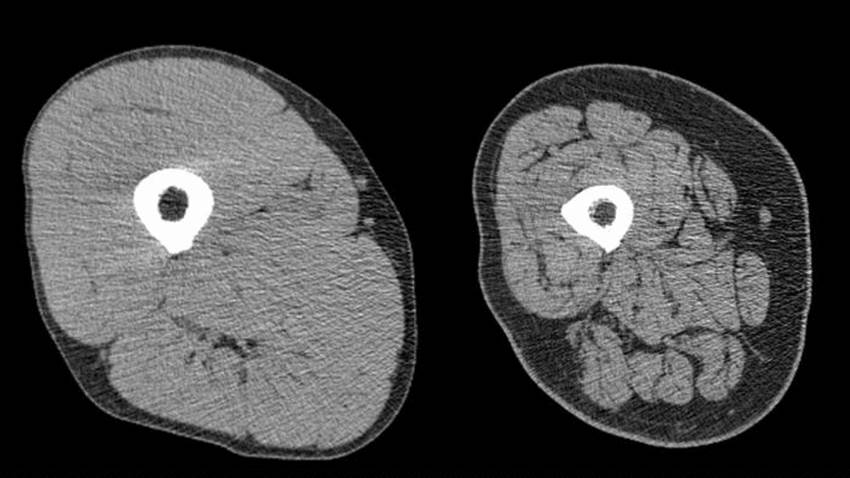

La sarcopenia es un factor de mal pronóstico en pacientes que usaron quimiorradioterapia, según estudio

Este estudio tuvo como objetivo investigar el efecto de la sarcopenia en el pronóstico de pacientes con cáncer de recto inferior avanzado, que reciben...